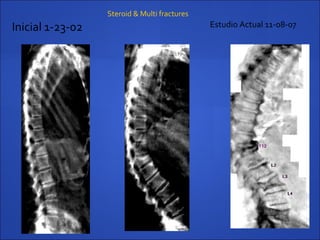

Inicial 1-23-02 Estudio Actual 11-08-07

T12

• #41 Fractura sintomatica G 3 en T12, y fractura G1y2 en T9,T11yL2